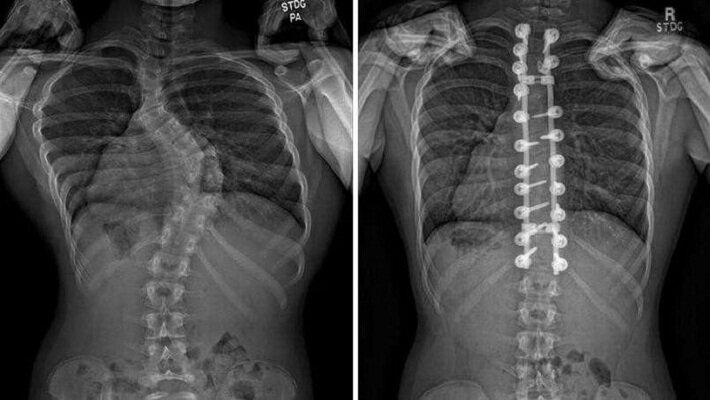

وی با اشاره به اینکه انحراف ستون فقرات میتواند بر عملکرد ریهها تأثیر بگذارد، گفت: تشخیص اسکولیوز معمولاً با معاینه بالینی توسط پزشک و استفاده از تصاویر اشعه ایکس صورت میگیرد چون بی توجهی به آن باعث اختلال در فعالیت ریهها میشود.

جراحی: در موارد شدید که انحراف ستون فقرات به ۴۰ درجه یا بیشتر برسد و یا موجب درد شدید، اختلالات تنفسی یا مشکلات عصبی شود، ممکن است جراحی لازم باشد. روشهای جراحی شامل فیوژن ستون فقرات یا اعمال پیچ و میله برای تثبیت ستون فقرات میشود.